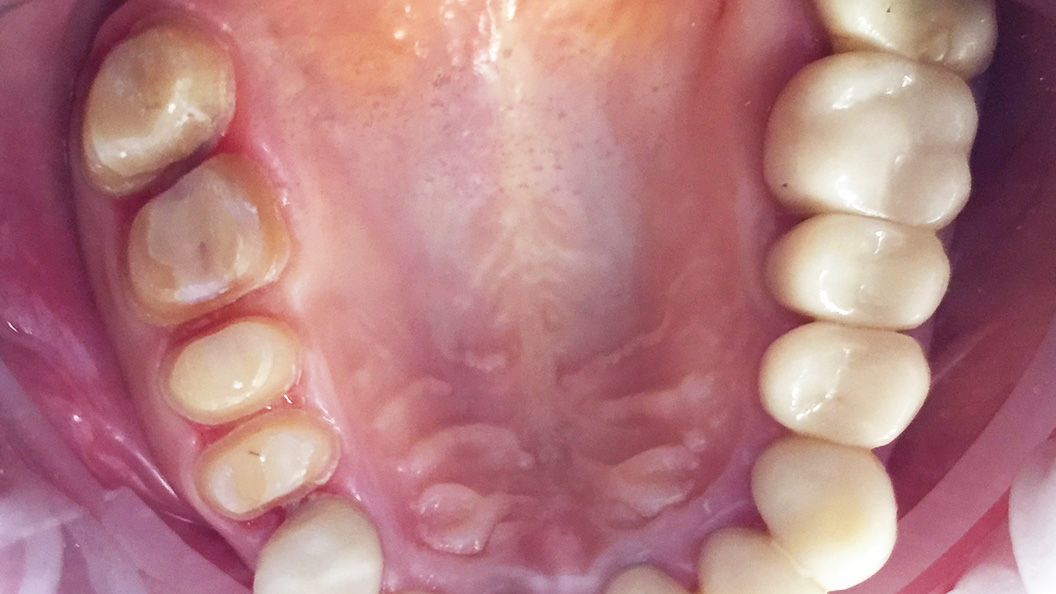

До и после лечения

В нашу клинику обратилась пациентка с целью восстановления эстетики зубов на верхней челюсти.

После осмотра и тщательной диагностики врач-ортопед Мельников Алексей Владимирович предложил протезирование коронками из цельной керамики.

В ходе лечения были проведены следующие работы:

- профессиональная гигиена полости рта;

- препарирование эмали зубов;

- снятие слепков;

- изготовление и установка цельнокерамических коронок на 15-17 зубы.